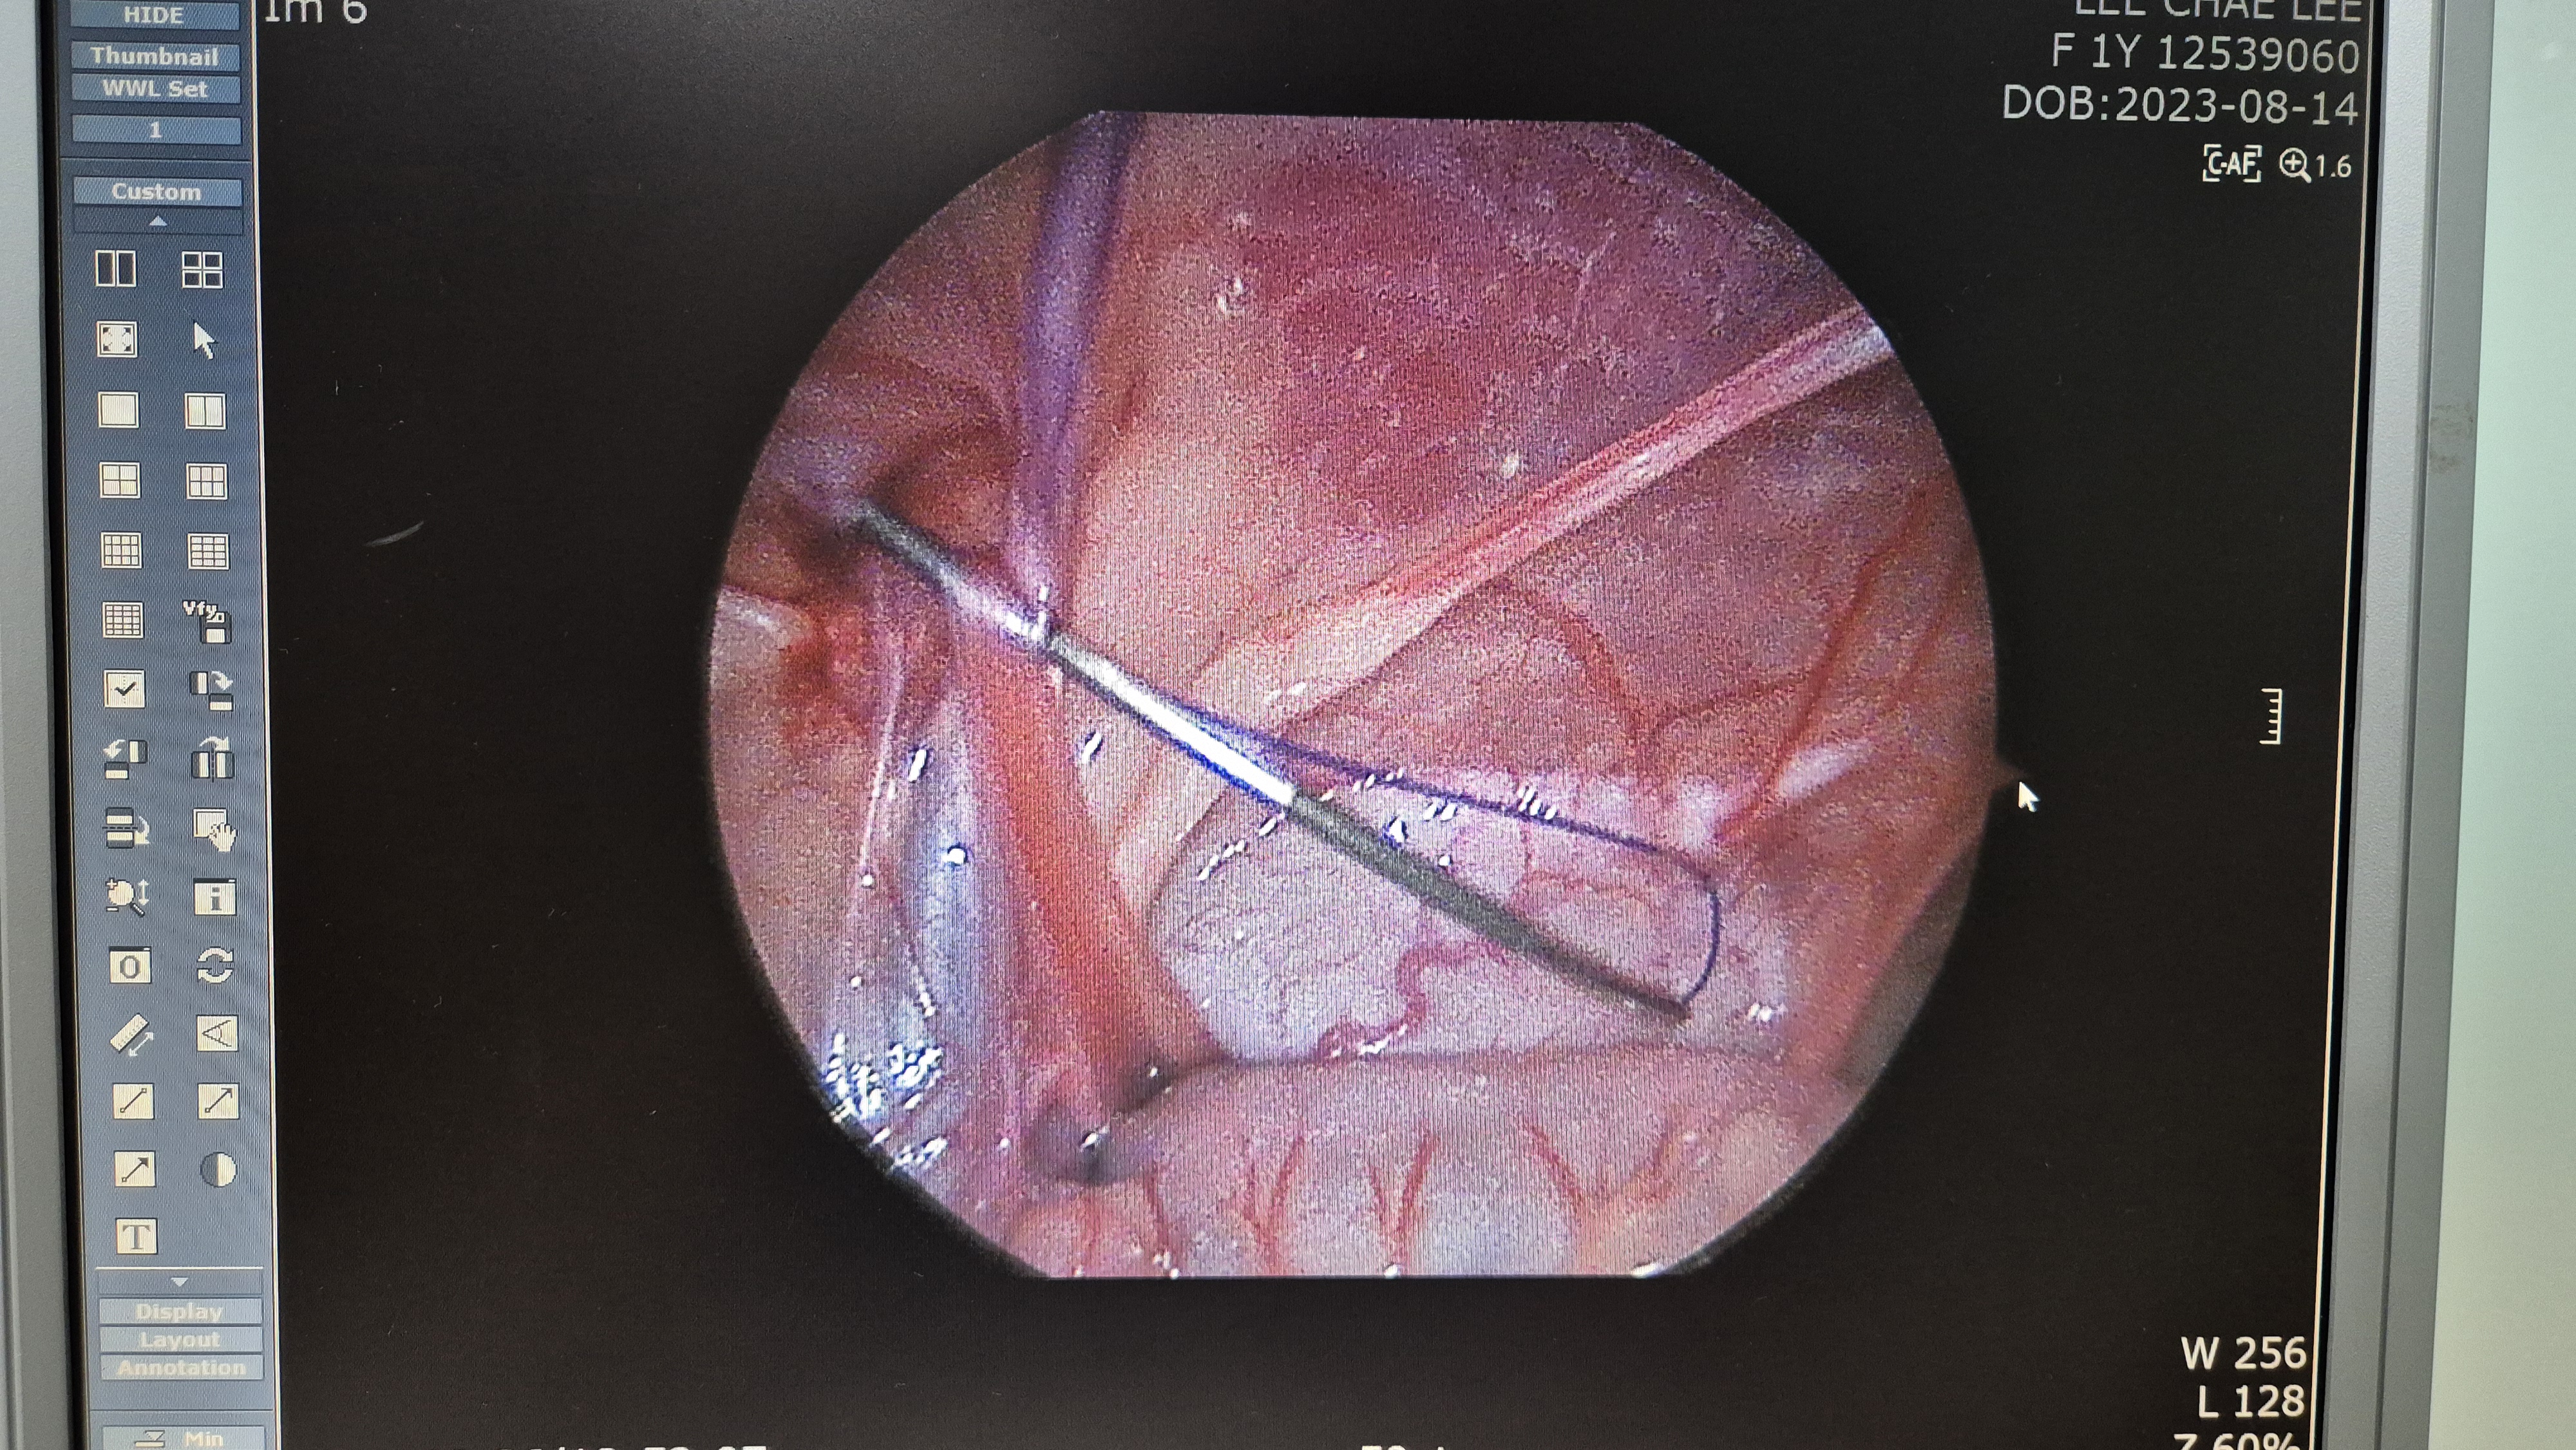

교정된 모습입니다. 탈장 구멍이 잘 봉합되었습니다.

탈장이 완전히 교정된 모습.